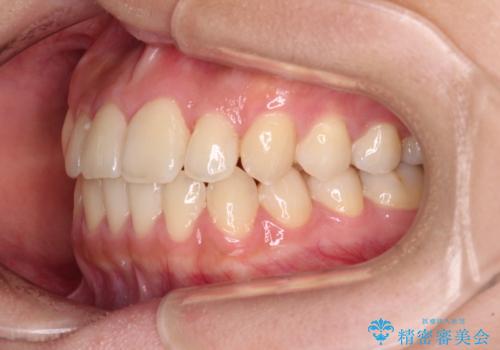

前歯のクロスバイトを短期間で解消 目立たないワイヤー矯正

- 前歯のクロスバイトを治したいとのことで来院された患者様です。

できる限り楽して、短期間で治したいとのことで、ワイヤー装置にて矯正治療を行うこととしました。